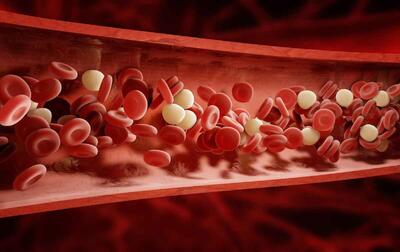

لخته شدن خون معمولا در کدام عضو بدن رخ می دهد؟ - خبرنامه

لخته شدن خون، یا ترومبوز، بخطرات جدی برای سلامتی دارد. عدم تحرک طولانی مدت، ضربه، اختلالات پزشکی و عوامل هورمونی از عوامل کلیدی هستند. افراد قد بلندتر به دلیل